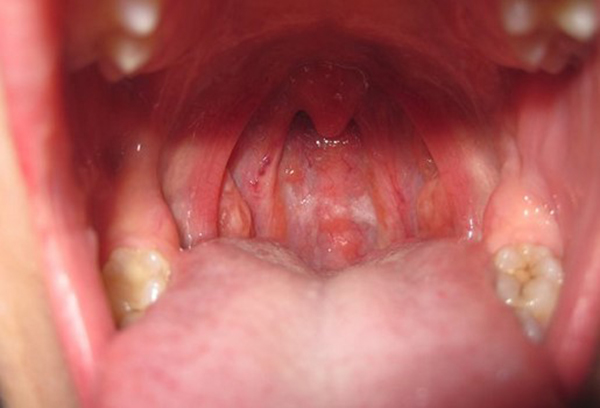

Tình trạng đau rát họng, sưng đau màn hầu, lưỡi gà xảy ra khi họng bị nhiễm khuẩn, thường gặp ở những bệnh nhân mắc bệnh viêm họng và viêm amidan, áp xe thành sau họng hoặc dị vật họng.

Nuốt vướng

Nuốt vướng là dấu hiệu của nhiều bệnh lý nguy hiểm về họng – thanh quản như: viêm họng – thanh quản, viêm amidan đặc biệt nguy hiểm hơn cả là ung thư vòm họng, ung thư thanh quản,…